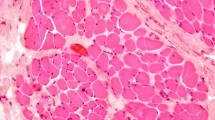

Relationship with the muscle and dermis: detailed histological findings

The following four regions of the ORL were examined histologically in detail: the periosteal, intramuscular, preorbicularis and dermal regions (Fig. 5). The detailed histological findings were almost entirely consistent with the morphological features evident in the mCT images. The periosteal elastin was continuous with that in the ligament and the dermis, while elastin was virtually absent from the perimysium. Type I collagen was found in the periosteum, perimysium, dermis and ORL. The muscle fibre did not join the ligament nor directly anchor to the dermis (column 4 in Fig. 5 and Supplementary Fig. S2). Even in the medial area, there was no muscle fibre below the bundles of the ORL even though the bundles were located very close to the palpebral portion of the OOc.

Like the mCT findings, the histological findings also presented a distinct intramuscular ramification of the retro-orbicularis fibres (row B in Fig. 5). Their fibroelastic tissue was usually separated from the perimysium. Elastin-positive ligamentous tissue of the retro-orbicularis fibres could be distinguished from the perimysium (Fig. 6). However, a few collagen fibres from the perimysium were confluent with the ORL (asterisks in Fig. 5).

Regional immunoactivity ratio of elastin to collagen type I in the four regions of the ORL presented in Fig. 5. All regions of the ORL contained elastin; the proportions were 25.6 ± 9.4% (mean ± SD), 9.8 ± 6.3%, 13.9 ± 8.7% and 38.1 ± 14.3% in the periosteal, intramuscular, preorbicularis and dermal regions, respectively. In contrast, there was no elastin in the perimysium. Each box plot shows the median, 25th and 75th percentiles, and range. The circle and asterisk indicate outliers.

As a declination of the preorbicularis fibres increased anteriorly, their orientation appeared approximately parallel to the skin (row D in Fig. 5). A dermal anchorage of the ORL was shown as a confluence of its fibroelastic tissue into the dermis.